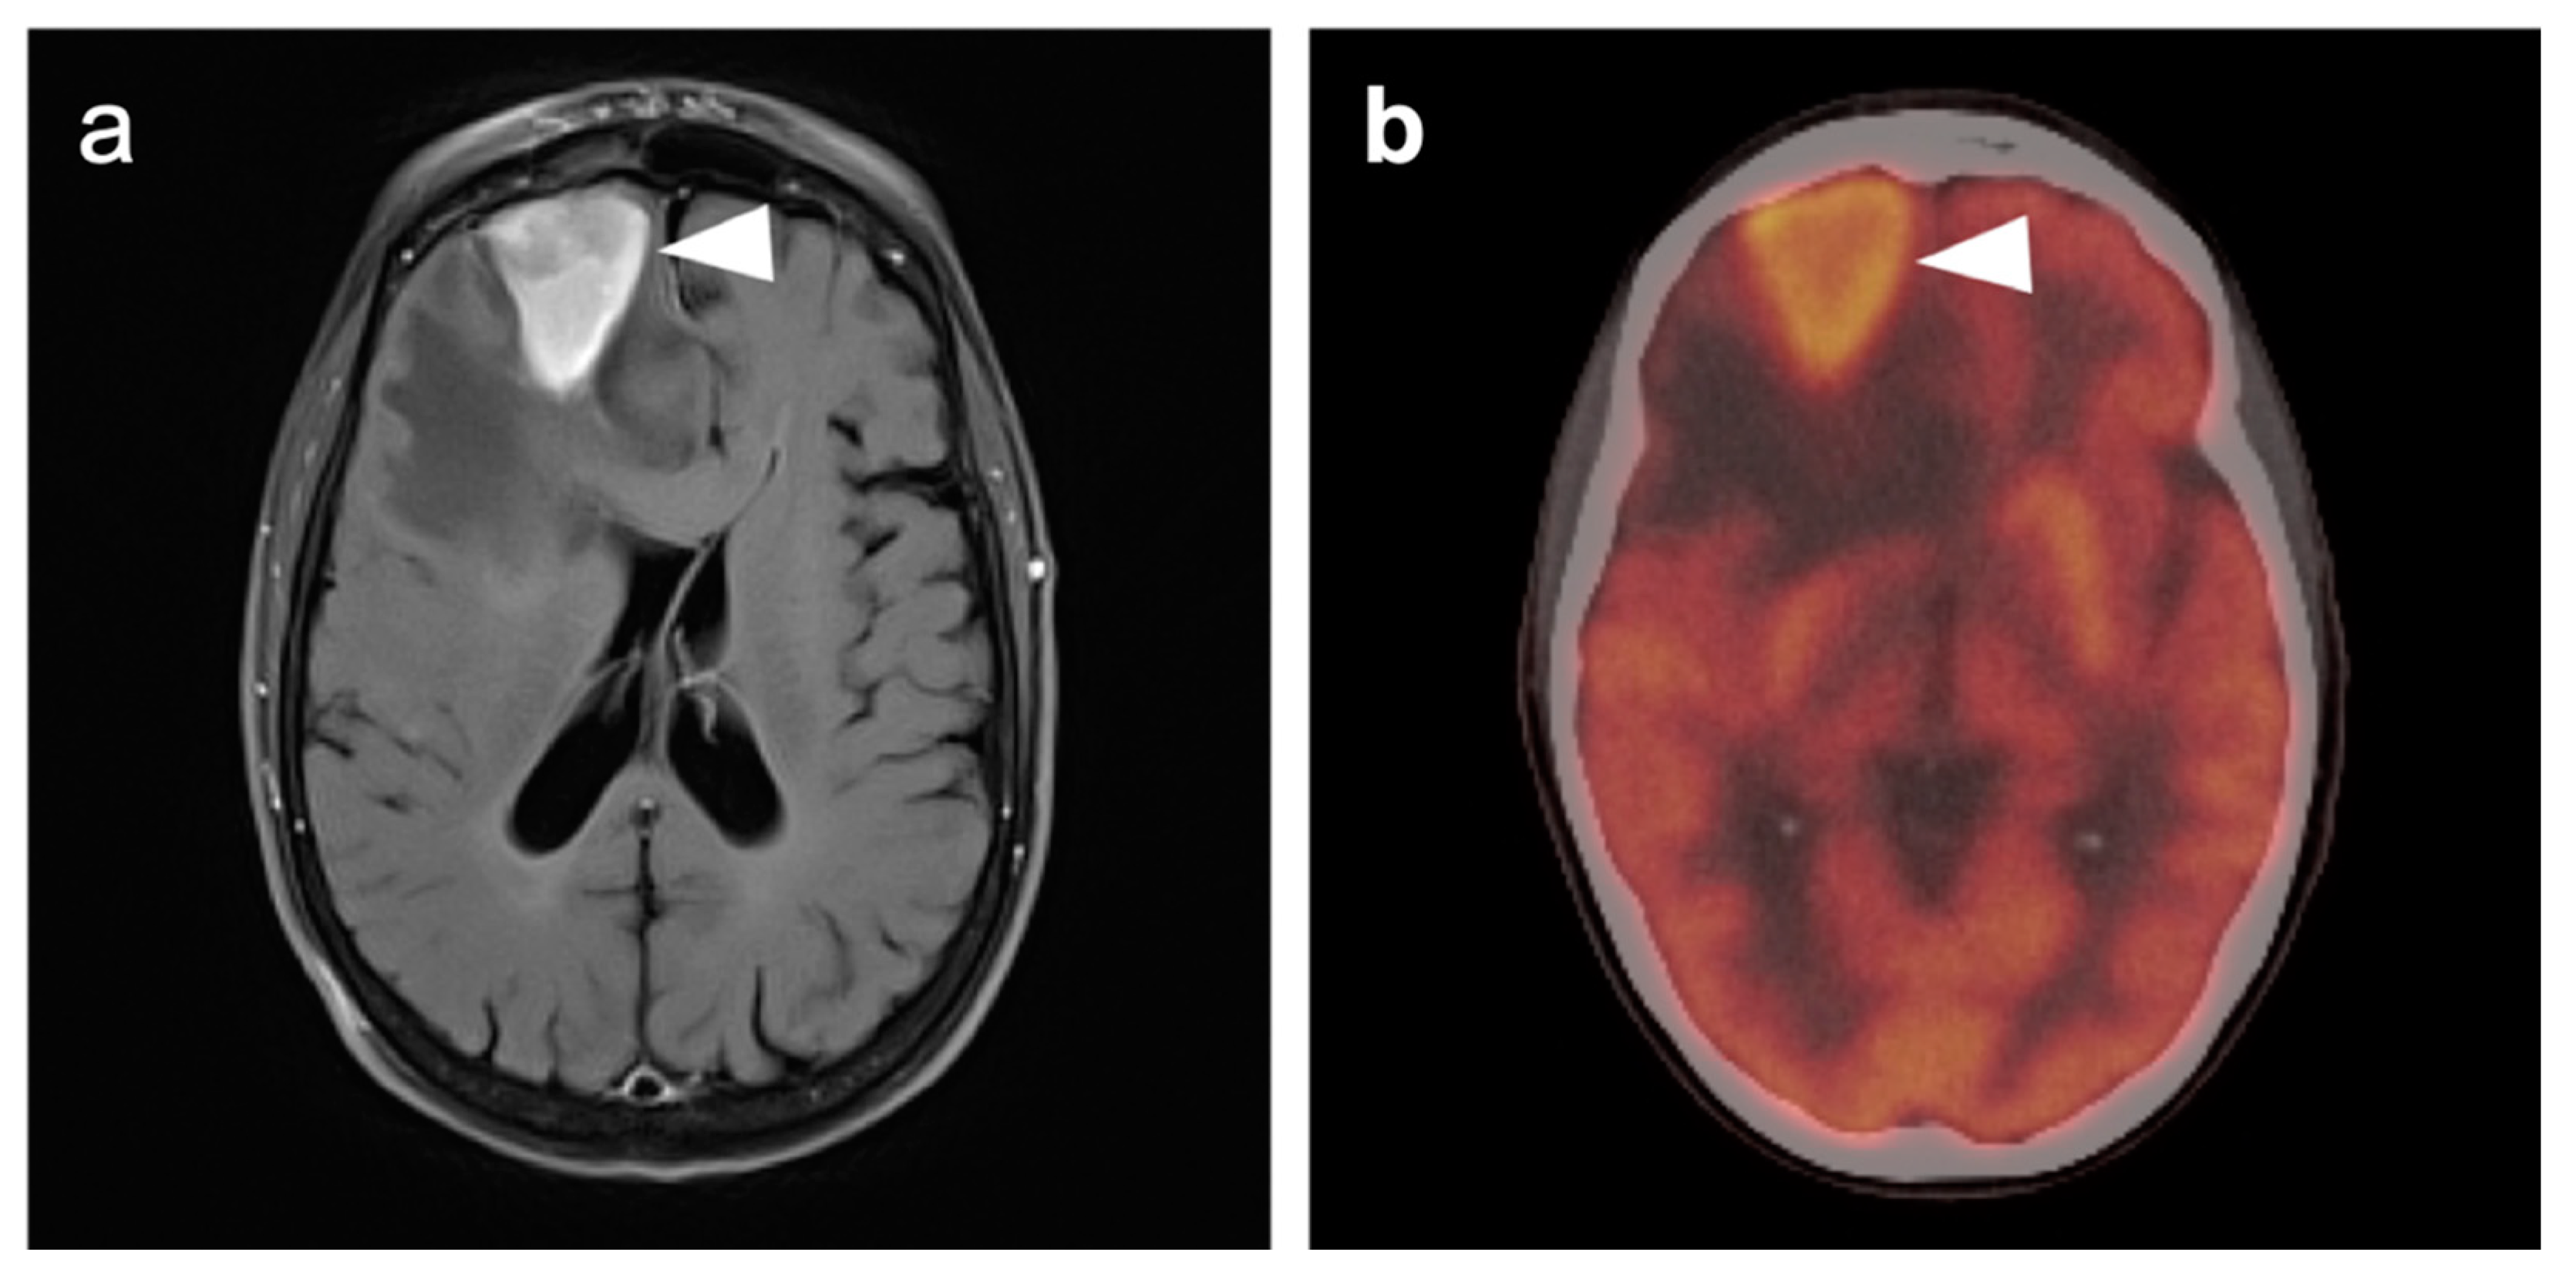

3.4. CNS Lymphoma

3.5. Brain Metastases

3.6. Response to Therapy